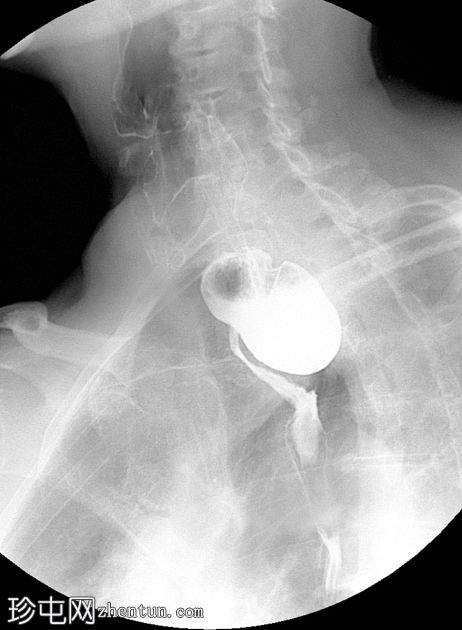

钡餐检查

透视

斜位

可见一充满造影剂的、向后突出的憩室,位于咽食管交界处后壁,大致在T1椎体水平。憩室颈部狭窄,与颈段食管相通。吞咽时憩室充满造影剂,延迟显像显示造影剂滞留。食管其余部分管径和走行正常。未见远端梗阻。

表现为后正中线向外突出的囊状物,颈部狭窄,位于 T1(C5-C6)水平或略低于该水平。

钡餐侧位片显示最佳。